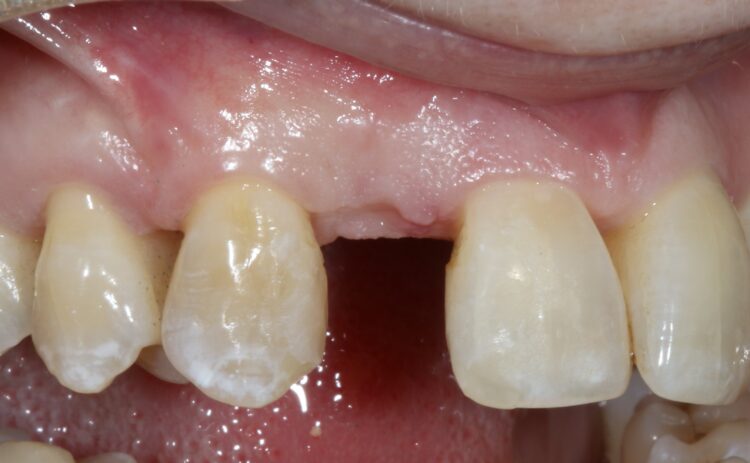

A female patient was referred for implant replacement of her failed upper right lateral incisor tooth. The tooth exhibited grade III mobility and had drifted forwards and downwards.

Clinical and CT scan assessment confirmed that the UR2 suffered from extensive bone loss with complete loss of the labial plate and was associated with a large periapical lesion which extended palatally and laterally towards the UR3. The UR3 tested positive to vitality testing.

It was considered high risk to attempt an immediate implant placement in such a compromised site and the treatment plan was to firstly remove the tooth and the granulation tissue and perform a simultaneous ridge preservation procedure to combat the likelihood of severe shrinkage of the socket during the healing period. The rationale was to fill the bone defect with a bone graft material immediately after tooth removal to reduce the shrinkage of the socket and maintain most of the socket dimensions during the healing phase.